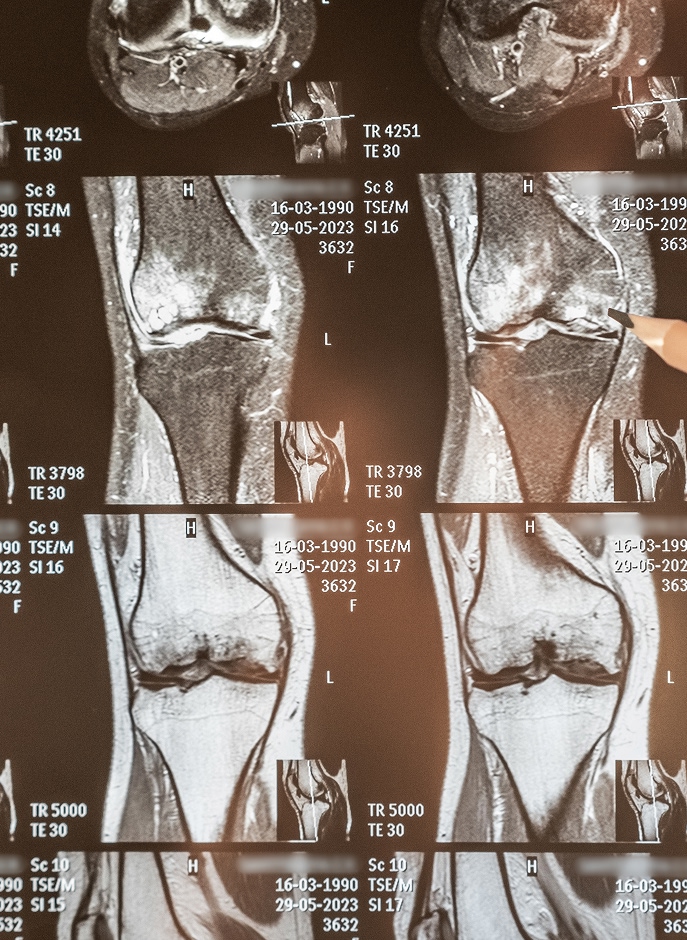

Una radiografía de rodilla es un estudio con rayos X (también lo verás como RX) que genera imágenes principalmente de las estructuras óseas: fémur, tibia, rótula y su relación (alineación y espacios articulares).

Si tu preocupación es el cartilago de la rodilla, es importante saberlo con honestidad: el cartílago no se ve directamente en rayos X, pero sí se observan signos indirectos (como disminución del espacio articular). En algunos casos, el médico puede complementar con tomografía o ultrasonido según la sospecha clínica.

RX (radiografía): rápida, accesible, ideal para hueso, alineación y signos de artrosis.

Puede mostrar alteraciones óseas, alineación, signos compatibles con desgaste (como en artrosis de rodilla leve u osteoartrosis en la rodilla), fracturas o sospechas según el caso. Para tejidos blandos, el médico puede pedir ultrasonido o tomografía si lo considera.

No lo muestra directamente. Pero sí puede evidenciar señales indirectas (por ejemplo, reducción del espacio articular). Si el foco es menisco, ligamentos o cartílago, tu médico decidirá si necesitas otro estudio complementario.